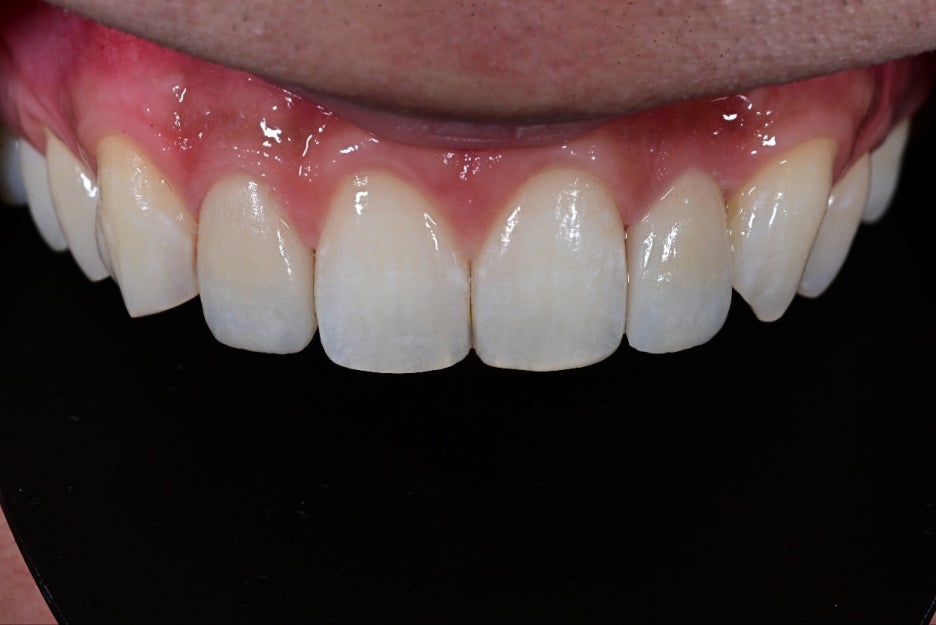

일주일 후 오브제로 라미네이트를

환자분의 입 안에서 실제로 확인했습니다.

이 과정에서

왼쪽 치아 풍융부(앞쪽 볼록한 부분)

오른쪽 치아의 옆면 볼륨

이 두 요소가 환자 얼굴형과 미소 라인에 가장 잘 어울리는 방향으로 미세 조정되었습니다.

두 치아의 가장 자연스러운 볼륨을 찾아

수정한 뒤 최종 접착을 진행했습니다.